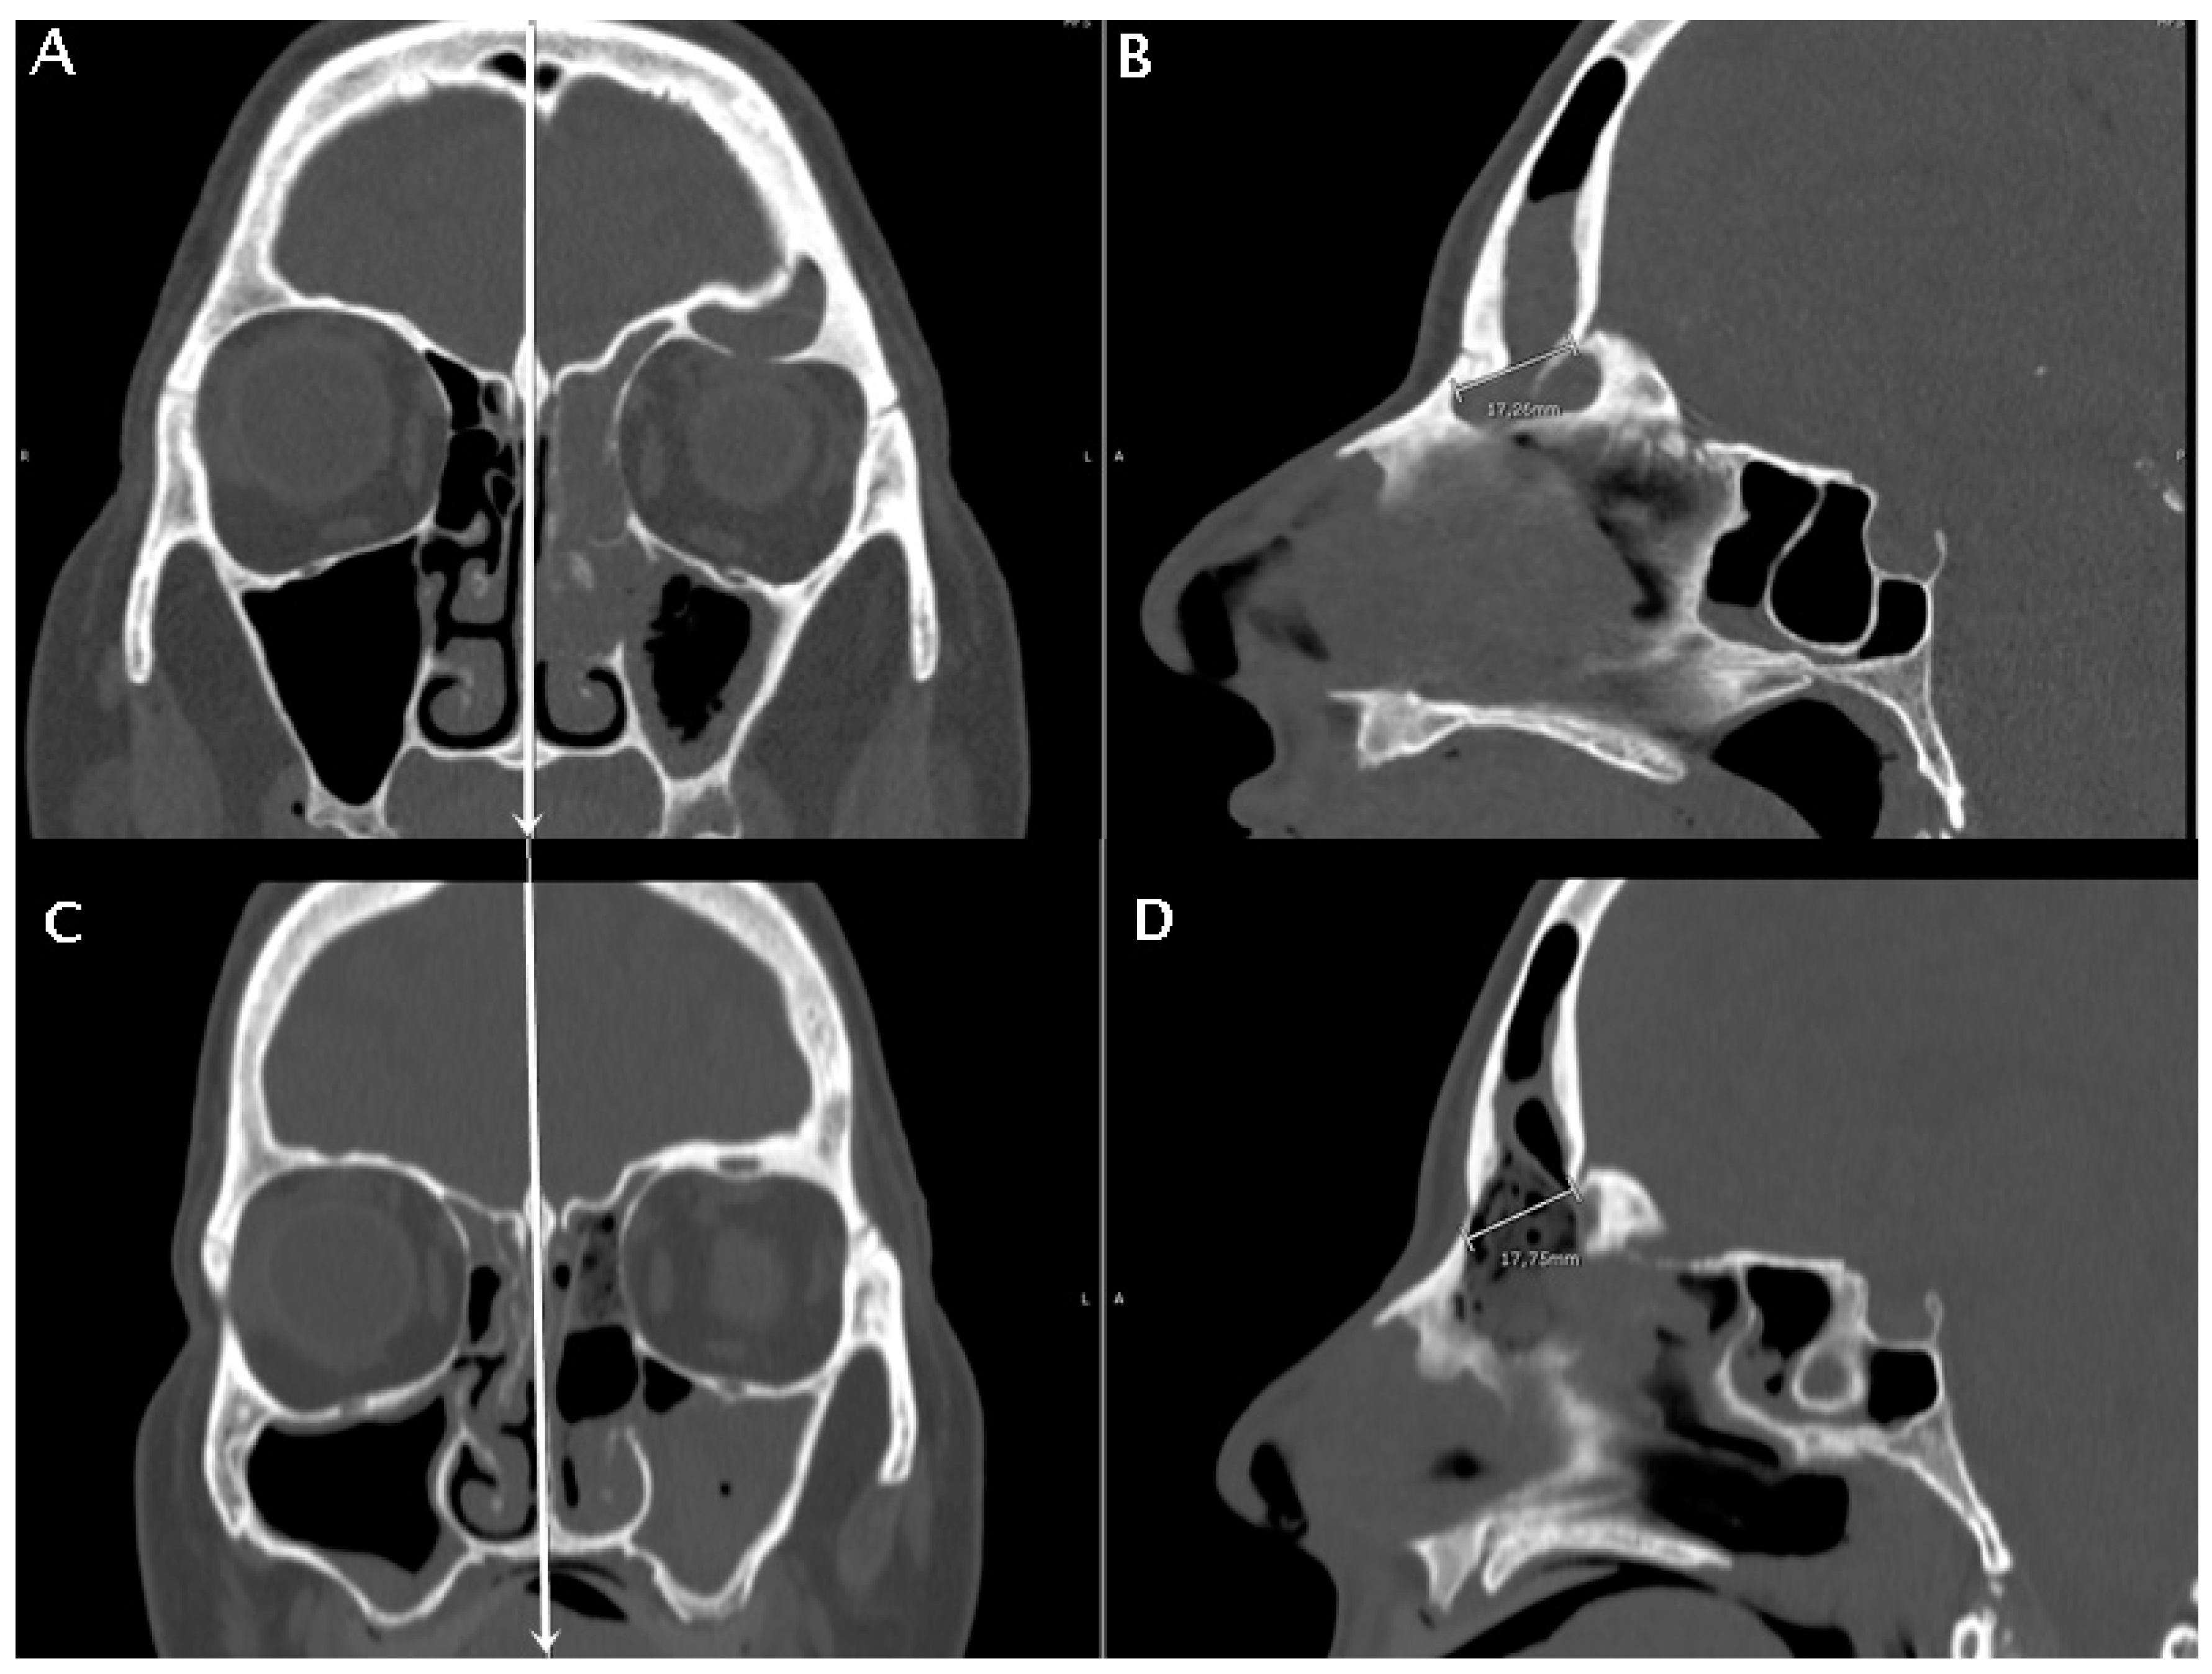

Figure 5. A patient with fronto-ethmoidal inverted papilloma undergoing a DRAF III surgery. The pre-operative CT scan is in (A,B), the post-operative CT scan is in (C,D). Coronal sections are used to identify the mid-sagittal line by the location of nasal septum and crista galli (white vertical lines in (A,C)). The anteroposterior diameter of the frontal sinus ostium is then measured pre- and post-operatively on mid-sagittal sections (B,D). The anteroposterior diameter of the frontal sinus neo-ostium in the post-operatory mid-sagittal images (D) was termed the obtained diameter (OD).

High-resolution CT images were analyzed from all the patients included by two authors (C.C. and M.B.). Mid-sagittal images, identified by the location of the nasal septum and crista galli, were chosen for analysis and measurement. The minimum and maximum frontal sinus outflow anteroposterior diameters (FOAP min and FOAP max, respectively) were measured. The FOAP max was measured as the sum of 1) the mid-sagittal anteroposterior thickness of the nasal beak and 2) the mid-sagittal anteroposterior distance between the nasal beak and the anterior most skull base (Figure 2), as described in the study by Zhang et al. It corresponds to the distance between the nasion and the posterior wall of the frontal sinus.

In the subset of patients with available early post-operative CT scan, a post-operative radiological parameter was measured, that is the obtained diameter (OD). It was calculated on the same mid-sagittal section of the pre-operative CT scan, as the distance between the most anterior portion of the frontal neo-ostium and the most anterior portion of the anterior skull base, as shown in Figure 5. A correlation analysis between the FOAP min, FOAP max, and G-N angle with OD was performed by means of the Pearson correlation coefficient for continuous variables.